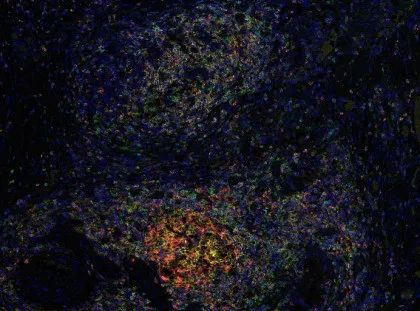

对于有特殊实验需求的客户,还有多重荧光免疫组化试剂盒,能够满足多指标的染色需求。多重荧光免疫组化试剂盒提供从4色到7色的解决方案,爱必信也为有需要的客户提供多色的实验服务。

五色荧光组化染色试剂盒(鼠兔通用二抗)

货号:abs50013